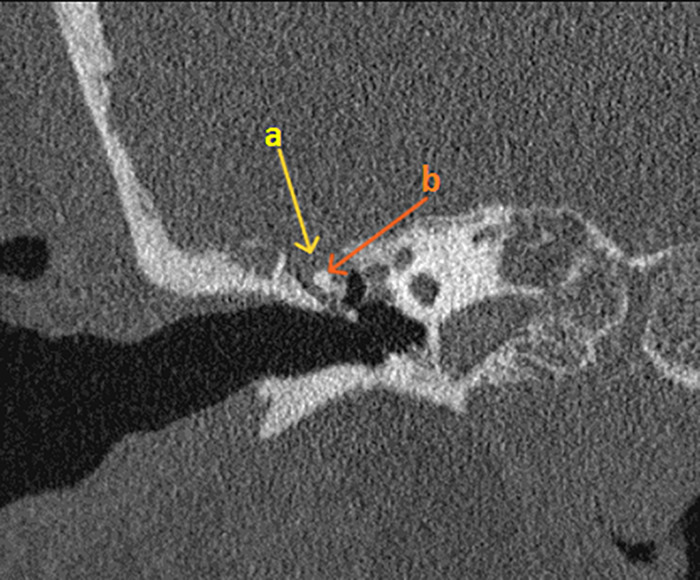

我们报告一例74岁女性头痛,发热,并间歇性右侧耳漏和鼻漏。她的鼻分泌物β -2-转铁蛋白检测呈阳性,证实脑脊液(CSF)泄漏。高分辨率CT (HRCT)显示右侧乳突、中耳和乳突空气细胞内的脑脊液缺损。钆增强脑MRI示侧脑室枕角弥散加权成像(DWI)高信号,DWI-表观弥散系数(DWI- adc)低信号,与脑室炎一致。经过六周的抗生素静脉注射后,她平静地康复了。病人接受手术修复骨缺损以防止复发。这是一例罕见的脑室炎合并自发性脑脊液泄漏的病例,没有现有的诊断标准,死亡率高。高临床怀疑辅助适当的影像学和多学科的方法来管理是必不可少的。

We present a case of a 74-year-old woman with headaches, pyrexia and intermittent right-sided otorrhoea and rhinorrhoea. Her nasal discharge tested positive for beta-2-transferrin, confirming a cerebrospinal fluid (CSF) leak. High-resolution CT (HRCT) mastoids showed a defect in the right tegmen, and CSF within the middle ear and mastoid air cells. A gadolinium-enhanced MRI brain showed high signal in the occipital horns of the lateral ventricles with diffusion-weighted imaging (DWI) and a low signal with DWI-apparent diffusion coefficient (DWI-ADC), consistent with ventriculitis. She made an uneventful recovery after 6 weeks of intravenous antibiotics. The patient had surgical repair of bony defects to prevent recurrence. This highlights a rare case of ventriculitis associated with a spontaneous CSF leak, with no existing set diagnostic criteria, and high mortality. High clinical suspicion aided by appropriate imaging, and a multidisciplinary approach to management are imperative.